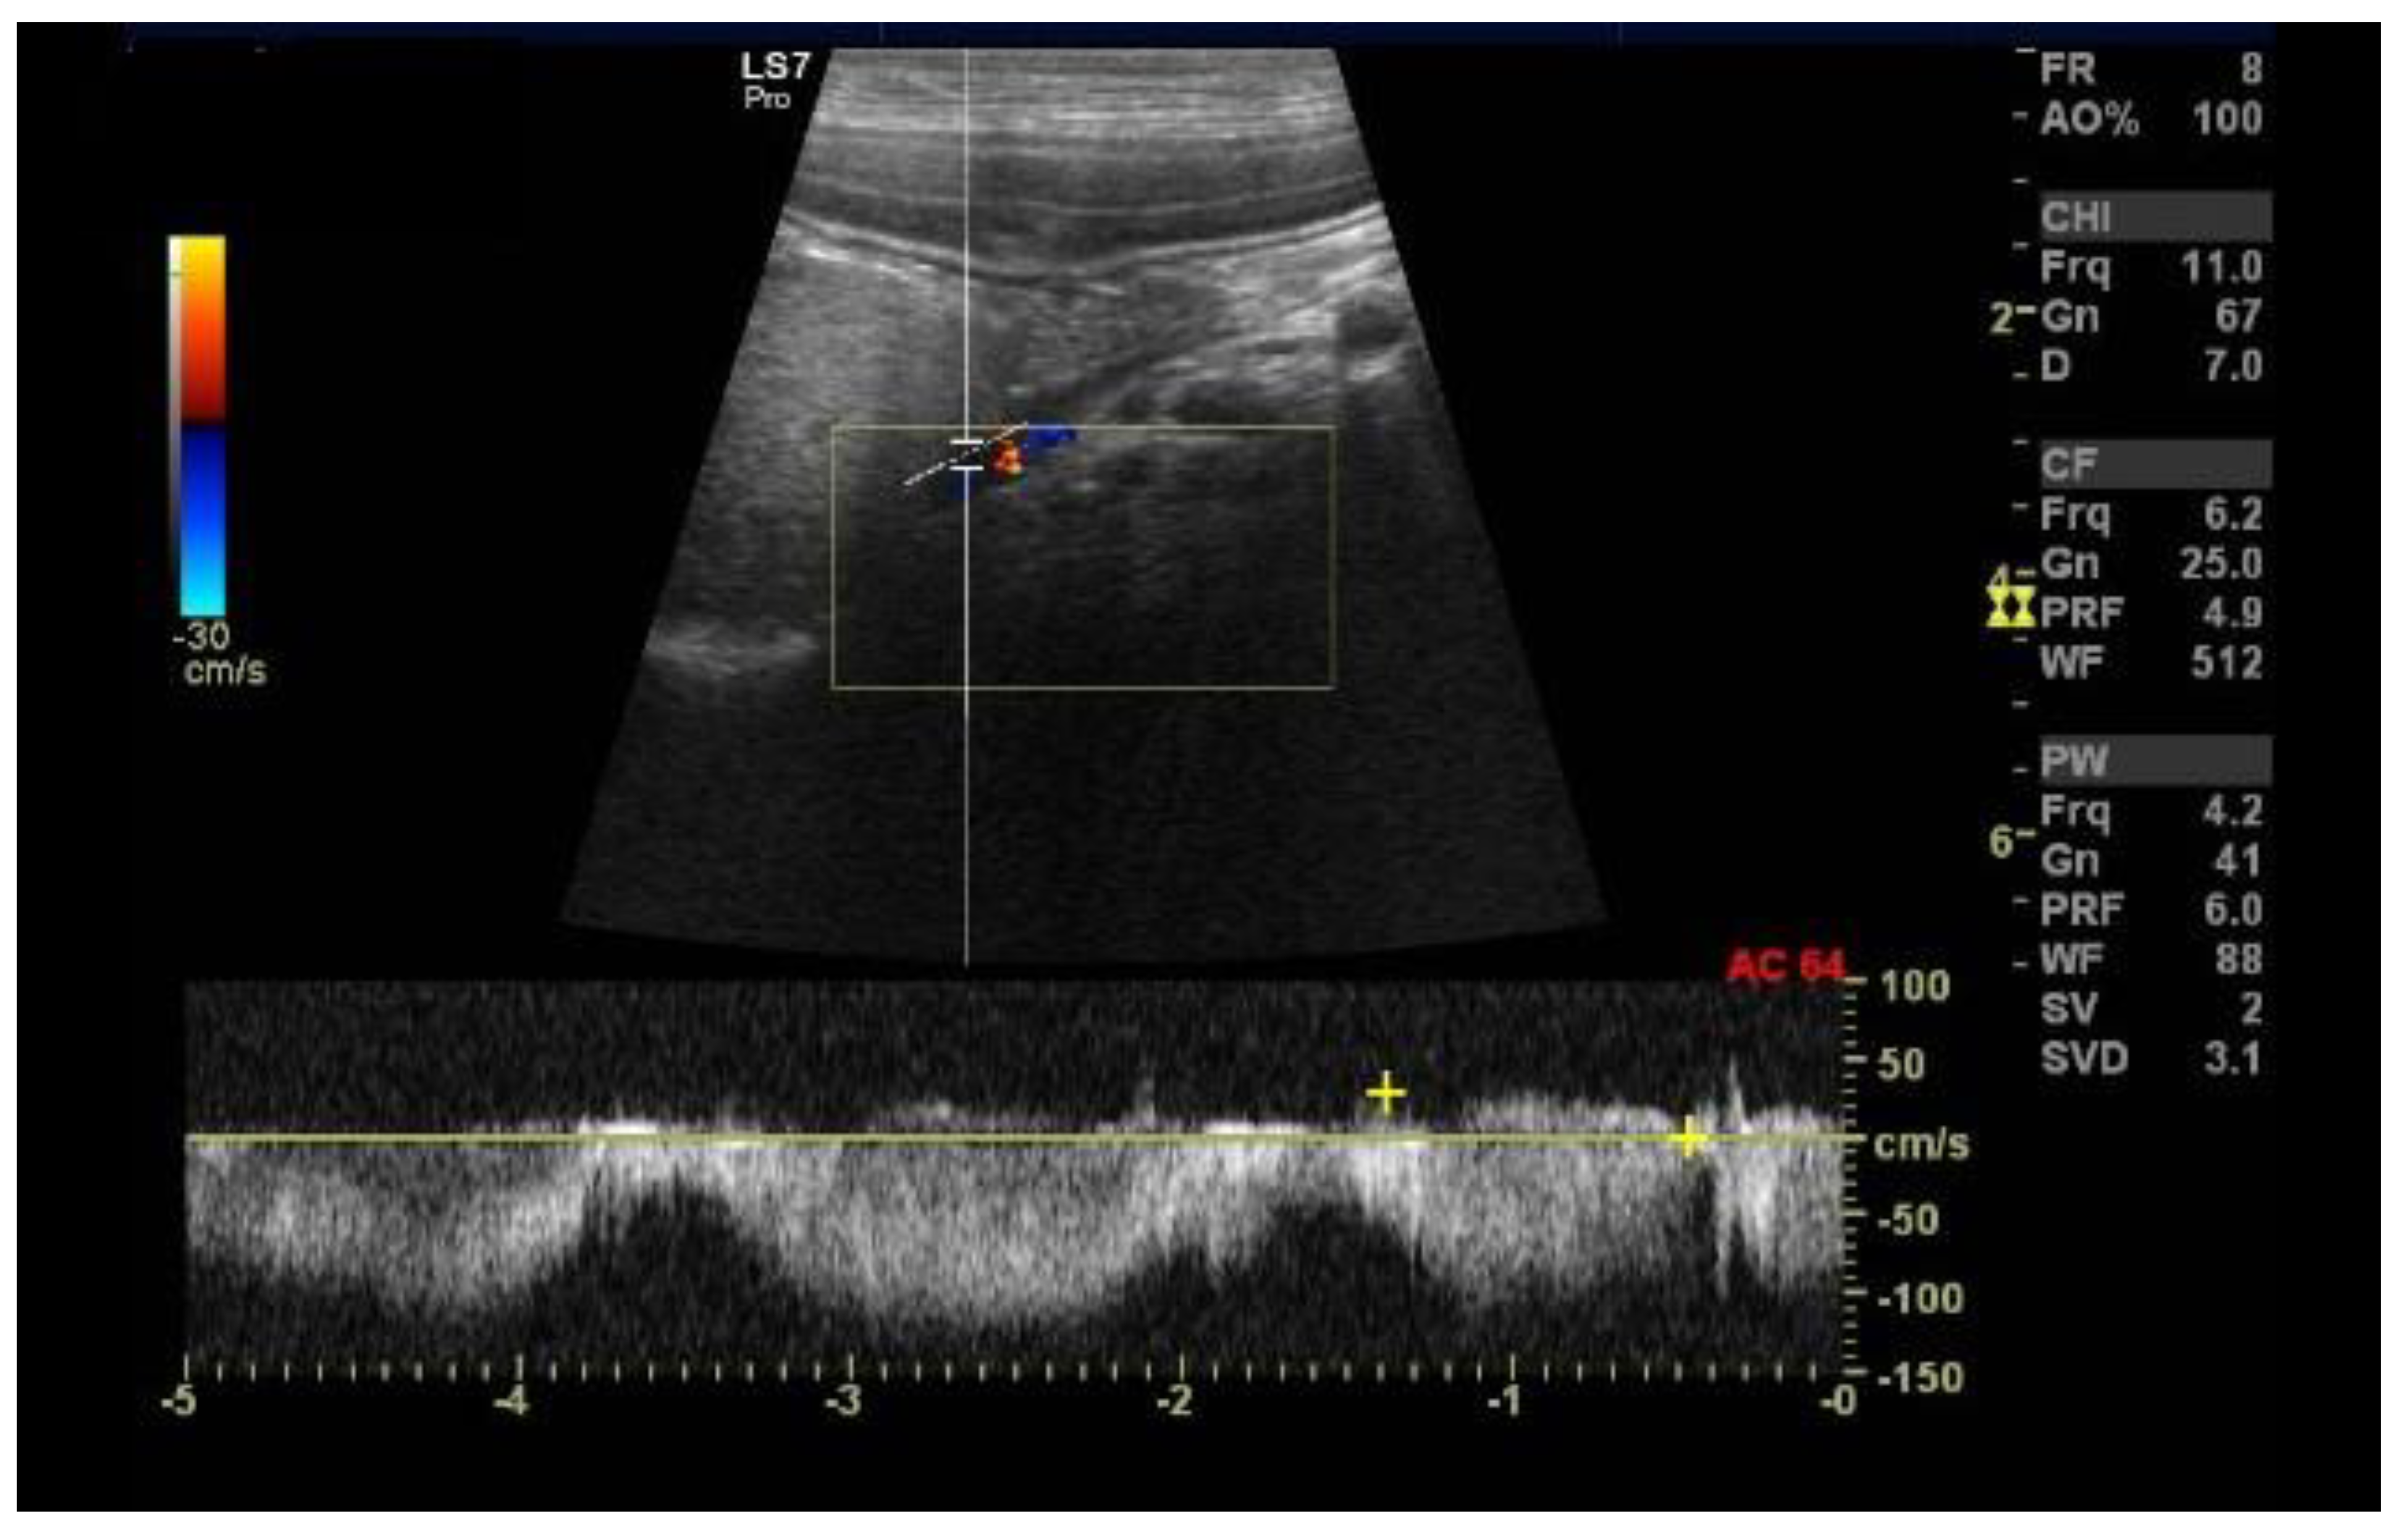

2.3. Case C (Dog)

2.4. Case D (Dog)

2.5. Case E (Cat)